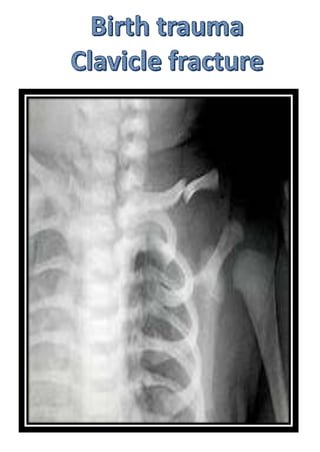

Multiple healing fractures